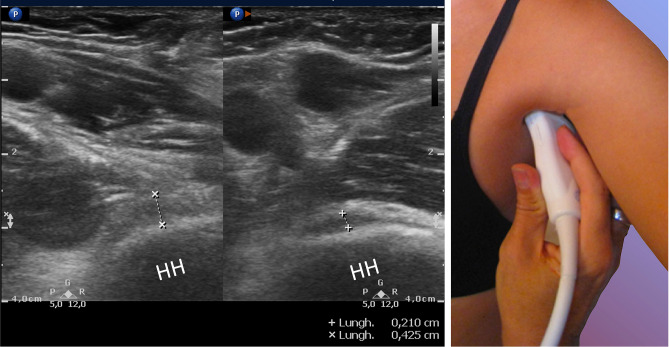

Axillary pouch thickening

Since Michelin et al. in 2012 [22] firstly investigated the inferior glenohumeral capsule thickening by studying AP/IGHL width in 20 patients with AC, and describing a significant widening of the AP and/or IGHL in contracted joints (4 mm), many papers documented the importance of evaluating AP in suspected AC [25, 26, 29] (Figs. 5, 6). Similar results are reported by Kim [23] who confirmed in a larger study the thickening of the AP in a larger cohort. Subsequently, Sernik et al. [24] documented a good correlation between AP thickening via the US (when higher than 2 mm) with MRI findings in 23 patients diagnosed with AC. Do et al. in 2021 [21] too, studying AP thickening, provided highly sensitive cut-off values useful for diagnosis. Meanwhile, Lee et al. [25], investigating the inferior joint capsule thickness in 71 patients with AC, documented that an AP of 3.2 mm thickness (with the arm held in a neutral position) had the highest diagnostic accuracy with a sensitivity of 73.2% and specificity of 77.5%. In this regard, Stella et al. [13] confirmed the importance of evaluating the AP thickening in patients with AC: an AP larger than 4 mm (mean 5.3 ± 1.15 mm) was detected in 99 patients (sensitivity 93.4% and specificity 98%) in comparison with the controls and with the contralateral shoulder (p < 0.0001); moreover, a difference in thickness higher than 60% was diagnostic for AC. Indeed, in this paper it is mentioned that in a previous preliminary study, using early-generation US equipment and poor-definition probes (7.5 MHz), there was the first identification of the AP abnormality, initially interpreted as a liquid (hypoechoic) distension of the axillary recess; the subsequent use of modern musculoskeletal US equipment revealed (2012) the hypoechoic “distension” as being the thickening of the AP. The mean AP thickening obtained from the studies presented in this review is 3.34 ± 0.8 mm [13, 15, 17, 21].

Fig. 5.

Oblique axial section: calipers shows the thickness of the axillary pouch in a patient with AC; the lest image is the contralateral side. HH humeral head

Axillar pouch and inferior glenohumeral joint in AC

Michelin et al. [22], were the first to document a significant thickening of the inferior glenohumeral joint capsule in patients with clinically and/or MRI-proven capsular contraction. Nevertheless, Stella et al. [13], affirmed that in 2004 they had begun a preliminary study of the features of the AP in patients with AC, noting an apparent expansion of the recess which was initially misinterpreted as hypoechoic joint effusion; the subsequent use of modern US equipment demonstrated (2012) that the hypoechoic image was a sign of the thickening of the joint capsule. However, a little amount of effusion may be present (in 13% of patients with AC) [13] between the meshes of the fibrous thickening of the AP due to the entrapment of synovial fluid as a result of capsular contraction. Subsequently, another group of study [15] documented AP and CHL thickening using MRI as reference: not only did they evaluate shoulders with B-mode, but by using CEUS they obtained higher sensitivities and specificities than sole grey-scale analysis. In recent years, several studies have evaluated AP thickening and provided useful cut-off values for AC diagnosis [13, 14, 16, 18, 21, 24], nevertheless, the group of study of Sernik et al. furnished those with the highest sensitivity and specificity [24]. Lately, Stella et al. [13], who examined the largest group (106 patients) ever studied with the US for AC, suggested their cut-off values for AP thickening. Furthermore, they also considered diagnostic for AC a difference in thickness of more than 60% between the contralateral pouch.